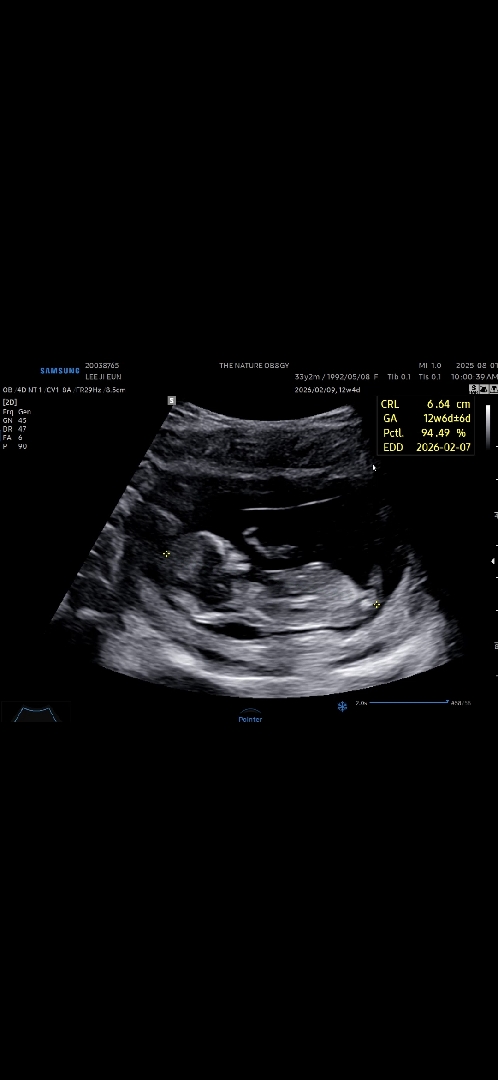

12주 각도법 성별 좀 봐주세요~

딸일까요 아들일까요?